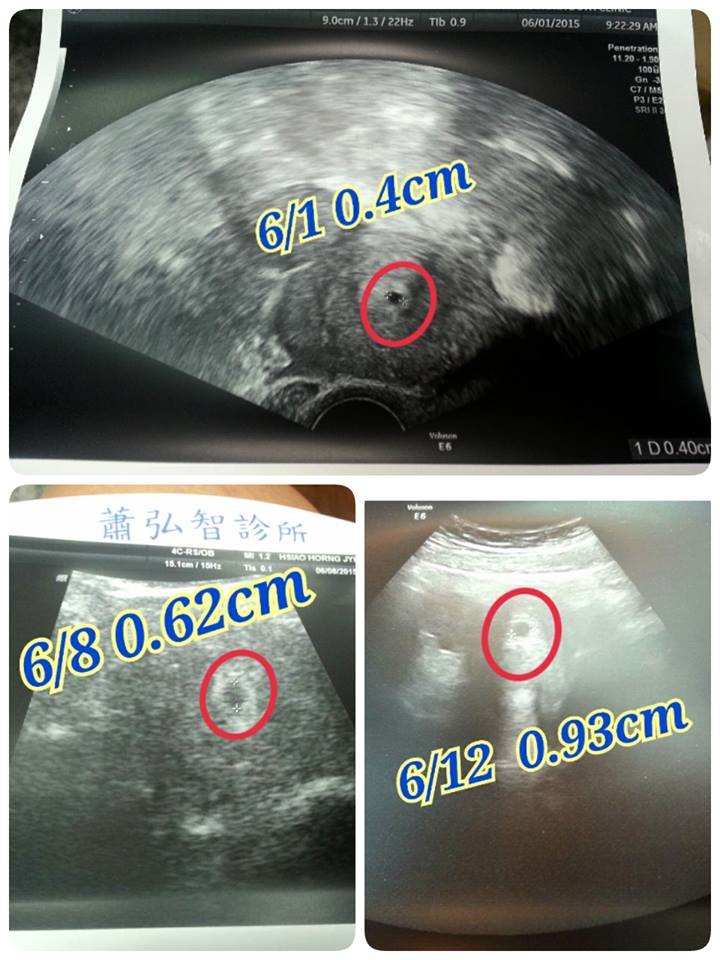

5/31驗孕發現兩條線..

隔天6/1去醫院照到胚胎..

醫生說 胚胎有在長大就好 不用太擔心 只要多休息就好

但是我還是好擔心..怕寶寶太小 長不大..